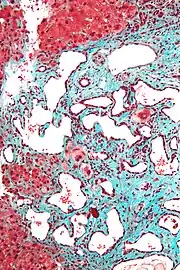

Micrograph of a bile duct hamartoma. Trichrome stain. Intermediate magnification

Micrograph of a bile duct hamartoma. Trichrome stain, high magnification

Low magnification micrograph of a bile duct hamartoma. Trichrome stain.